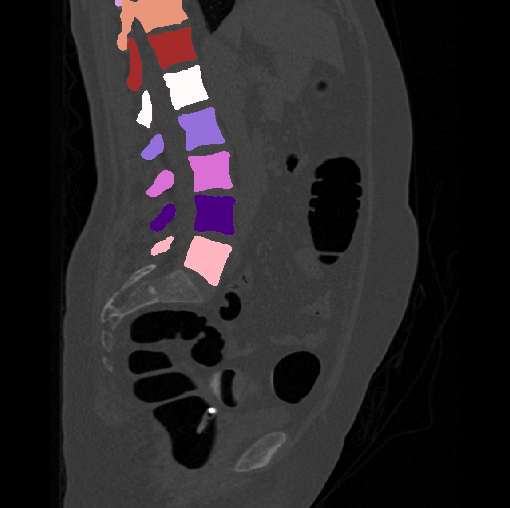

Spinal imaging via computed tomography (CT), magnetic resonance imaging (MRI), radiography, ultrasound, positron emission tomography (PET), and other radiologic imaging modalities is essential for noninvasively visualizing and assessing spinal pathology. Computational methods support and enhance a physician’s ability to utilize these imaging techniques for diagnosis, noninvasive treatment, and intervention in clinical practice. Analysis algorithms developed in the field of computer vision, computer graphics, signal processing, and machine learning have been adapted to analyze spinal images (Li et al., 2015). Conventionally, CT is preferred to study the spine due to a high bone-soft tissue contrast. There are diverse image appearance variations due to differences in vertebral position, metal artifacts and spinal diseases, etc., challenging the analysis algorithms. Fig. 1 gives some examples of these various conditions.

We calculate the two metrics of each vertebra, and the results are reported in Table 2. On the one hand, our experimental results are close to those reported in reference (Sekuboyina et al., 2020) with the same model (nnUnet), verifying the high quality of our annotations. On the other hand, Table 2 shows it is difficult to segment the diseased vertebrae (the DSC of L6 is almost 0). Specifically, the existence of L6 confuses the model, resulting in prediction dislocations (see the last row in Fig. 4). Thus, our labeled dataset, which contains many L6 cases, is very valuable for the diseased vertebrae segmentation (we have stated those cases that are hard for annotation in the readme.txt file). Table 2 illustrates that the model trained with our annotations can achieve good performance on our CTSpine1K dataset but a much worse performance on the VerSe Challenge datasets, which explains there is an obvious domain gap between our annotated dataset and the public dataset. We infer the reason is that the COlONOG dataset is based on an empty stomach and colon, confusing the deep learning model by the changes of air content in the abdomen (see Fig. 3). Therefore, our annotations are a good complement to the existing datasets.

3.2.2 Qualitative results.

Some visualization results are presented in Fig. 4, where we can observe that the baseline model can achieve excellent segmentation results. Nevertheless, some failed predictions occur when spinal diseases exist, especially sacral lumbarization and lumbar sacralization. Besides, the image’s resolution of Z direction is closely related to the results, and a lower resolution leads to worse results. Maintaining a reasonable performance for a low resolution is a research challenge. Image superresolution (Peng et al., 2020) might be worth exploring.